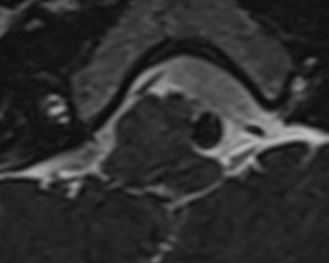

МРТ и МРА при долихоэктазиях сосудов головного мозга

Долихоэктазия означает расширение и удлинение сосуда. В ее основе лежит дефект соединительной ткани стенки сосуда и растяжение под действием артериального давления. Встречаются долихоэктазии крайне редко, с преобладанием у мужчин. Причины точно неизвестны, часть из случаев связана с атеросклерозом или расслоением сосуда. Долихоэктазия обычно сопровождается гидроцефалией. Клиника зависит от сдавления близлежащего черепного нерва. Из всех долихоэктазий чаще других при МРТ в СПб мы сталкивались с долихоэктазией базилярной артерии и, иногда, одновременно и ее ветвей. При МРТ головного мозга также нам приходилось наблюдать долихоэктазию ВСА. При любом варианте долихоэктазии на Т2-взвешенных МРТ головного мозга видно расширение сосуда и расположение бифуркации базилярной артерии выше супраселлярной цистерны. При этом могут быть компримированы VII и V черепные нервы, очень редко другие. При МРА головного мозга видно, что артерия удлинена и расширена.

МРТ головного мозга. Т2-взвешенная аксиальная МРТ. Долихоэктазия базирярной артерии.